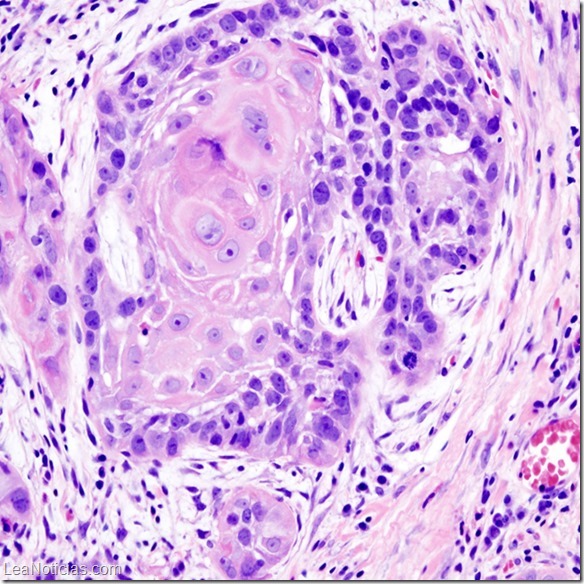

“El sistema inmunológico juega un papel importante en ayudar a nuestro cuerpo a mantener el cáncer e infecciones como el VPH bajo control. Cuando el sistema inmunológico se ve comprometido debido a la infección por el VIH, el cuerpo tiene más dificultad para controlar infecciones y, las complicaciones del VPH como el cáncer cervical y anal, son más probables de producirse. Por esta razón, es importante la revisión de rutina para las personas con VIH”, explicó.

“El VPH se transmite por contacto directo con la piel que está infectada con el virus. Cuando se produce el VPH en el área genital, puede ser transmitido sexualmente. Además del contacto de piel a piel con el pene, el escroto, la vagina, la vulva o el ano, el VPH puede ser transmitido a través del contacto de los genitales de su pareja con la boca. Las verrugas genitales son muy contagiosas y la mayoría de las personas que entran en contacto con una persona infectada desarrollarán las verrugas en sí mismos aproximadamente dentro de 3 meses”, explica la especialista, aunque también advierte que, en la mayoría de los casos, la enfermedad relacionada con el VPH (verrugas genitales o una condición precancerosa denominada displasia) pudiera no desarrollarse nunca, o tomar años o décadas antes de hacerlo.

Aclaró que la vacuna contra el VPH se destinó para ser utilizada en la prevención, pero no para tratar el curso de la infección por VPH. “La vacuna tiene como objetivo las cuatro cepas del VPH más asociadas con el cáncer cervical y las verrugas genitales, por lo que no puede ser protección contra otras cepas. Existen cepas de VPH que todavía pueden causar verrugas o cáncer. Si usted se vacuna, debe seguir realizando exámenes con regularidad”.